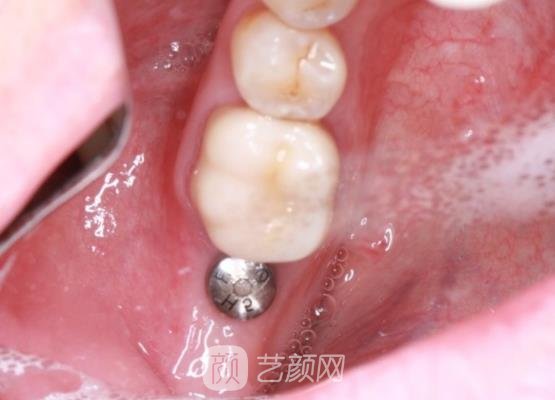

我一直以来渴望自己的牙齿变得更加健康整齐一些,但是我由于一次意外情况导致牙齿出现了缺失的问题,这种情况已经伴随了我很长时间,而且影响到了正常的咀嚼功能,对于这样的情况出现,我也感觉到很苦恼。于是为了改变,我决定到医院做种植牙手术。

等我了解了之后,医生就为我做了手术,过程比较的顺利,没有损害到口腔组织,术后还对我交代了一些相关的注意事项。之后我便回到家里休养了,在休养的阶段,我精心的护理着口腔。饭后我会及时的漱口,而且牙缝里的脏东西我也会利用压线来清洗,因为我怕出现感染问题。

而且我一直以来和医生保持联系,医生对我照顾的也很不错,我也到医院做了一次的复查,医生也说我恢复的很好。听到医生的夸奖,我的心里面真的也很开心,接下来的日子我还是要好好的护理,相信很快就会恢复好的,那样我的牙齿会变得更加健康整齐。

不知不觉一个半月过去了,通过我这段时间的精心恢复,现在牙齿恢复好了,变得很漂亮也很整齐。根本也看不出来是做过手术的,就连父母都替我感到高兴,同时我也很感谢医生。